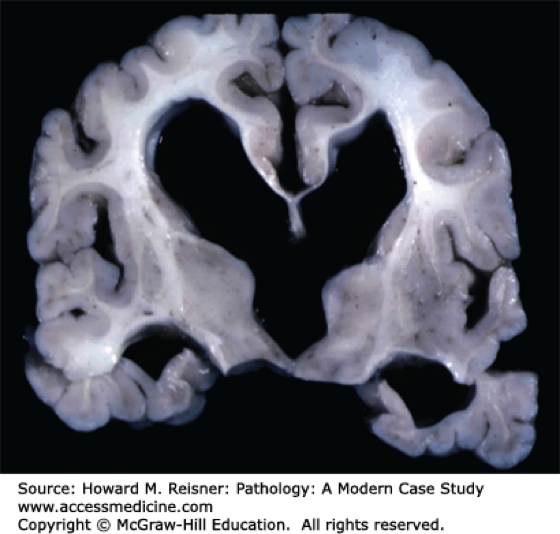

Figure 2.9. Enlarged lateral and 3rd ventricles. Pathology of the Nervous System, Reisner HM. Pathology: A Modern Case Study; 2015. Accessed July 27, 2018.

Non-communicating hydrocephalus—also called “obstructive” hydrocephalus—occurs when the flow of CSF is blocked in the ventricular system; this is the most common form of hydrocephalus (Figure 2.9). Congenital defects of the embryonic ventricular system involving faulty canalization/narrowing of passageways lead to this condition. Other causes may include tumors or abscesses.

• One of the most common locations of this narrowing is the cerebral aqueduct, aqueductal stenosis, between the 3rd and 4th ventricles.

• Other locations for obstructive hydrocephalus are where the lateral ventricles drain into the third ventricle at the interventricular foramen and where the 4th ventricle opens via the lateral foramina.

• Atrophy of brain tissue may also occur if non-communicating hydrocephalus remains untreated.